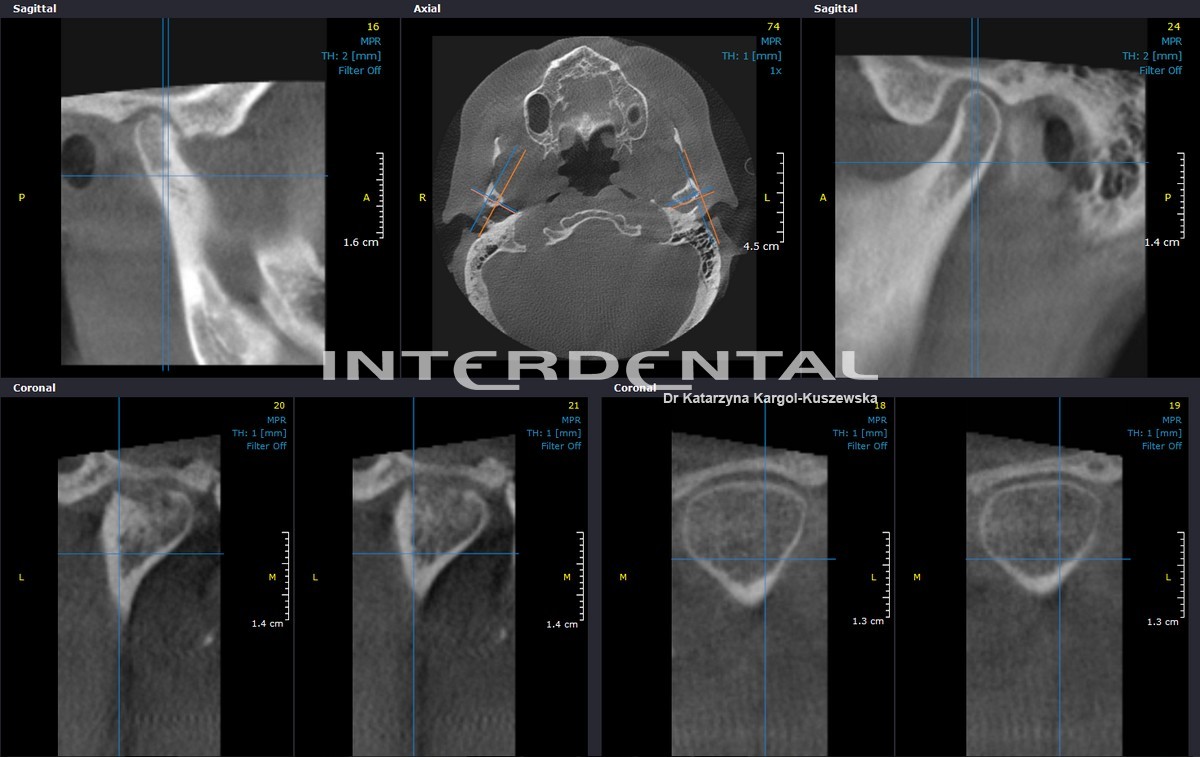

CBCT - tomografia komputerowa w stomatologii

CBCT (Cone-beam computed tomography in dentistry) – jest szybką a zarazem bezpieczną metodą obrazowania w radiologii stomatologicznej. Tomograf komputerowy CBCT pozwala na uzyskanie trójwymiarowego obrazu twarzoczaszki przy znacznie niższej dawce promieniowania w stosunku do konwencjonalnej tomografii komputerowej CT.  CBCT jest najdokładniejszą metodą obrazowania w stomatologii, chirurgii szczękowo-twarzowej oraz laryngologii.

W powstałym obrazie widoczne są kanały nerwowe, naczynia krwionośne, zęby, zatoki oboczne nosa. CBCT pozwala na obrazowanie wszystkich struktur anatomicznych z dokładnością niemożliwą do uzyskania w innym rodzaju badania radiologicznego. Uzyskany obraz można wielokrotnie przetwarzać, obrabiać, mierzyć i tworzyć wizualizację.

Zaburzenia stawu skroniowo-żuchwowego

• określenie położenia i funkcjonowania struktur stawu skroniowo-żuchwowego

• wizualizacja tkanek miękkich otaczających stawy skroniowo-żuchwowe